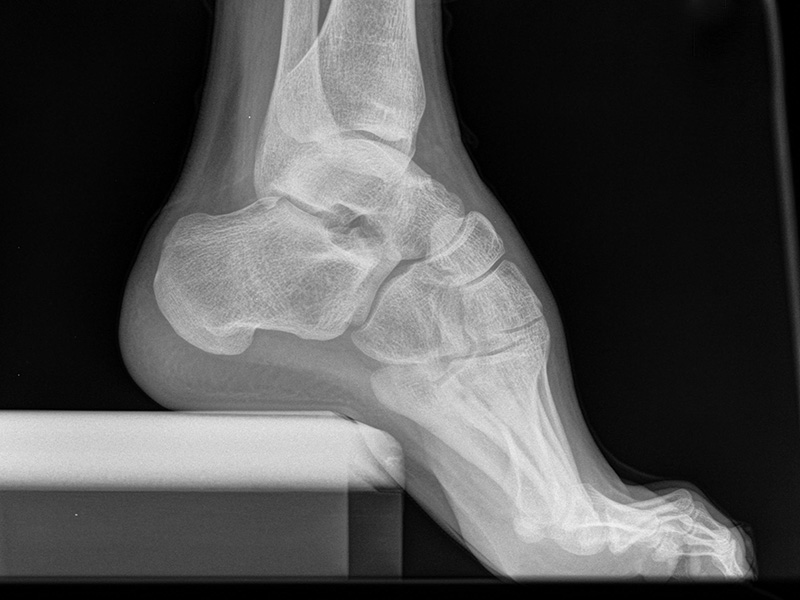

Sprunggelenk lateral ohne Belastung

Kennzeichen des Röntgenbildes:

• Oberes und unteres Sprunggelenk sind rein seitlich abgebildet, inklusive Kalkaneus.

• Die Malleolen kommen übereinander zu liegen.

• Tibiagelenkfläche und Talusrolle werden exakt seitlich dargestellt, es kommt zu keinen Doppelkonturen.

• Die Fibula projiziert sich ins mittlere bis hintere Drittel der Tibiagelenkfläche.

• Die vordere und hintere Tibiakante, das Chopart-Gelenk und das Subtalargelenk kommen zur Darstellung.

• Das proximale Ende des Os metatarsale V ist mit abgebildet.

• Der Weichteilmantel (Achillessehne) ist erkennbar.

Besondere Bemerkungen zum Beispielbild:

• Patient mit anamnestisch chronischer OSG Instabilität.

• Ventral der Tibia findet sich ein abgebrochener Osteophyt.